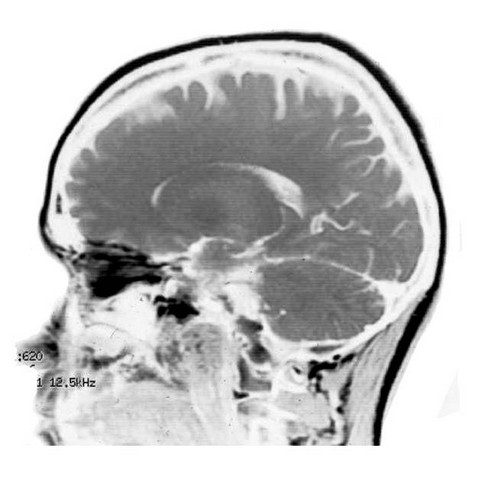

Neurología de la música y del lenguaje